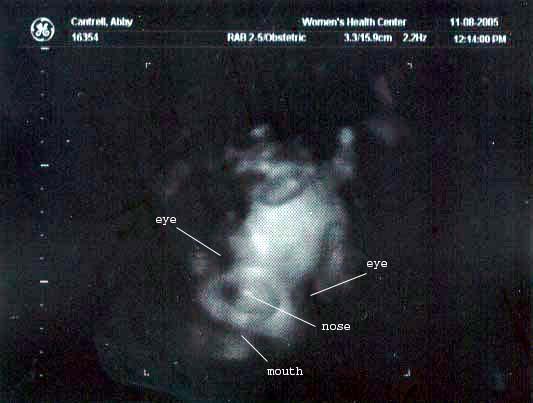

33 week ultrasound ~ 3D view of the baby's face, looking right at the "camera." Our little alien has really filled out!

33 week ultrasound ~ Eyes, nose and mouth labeled because it really is hard to see what you're looking at, even if you k...